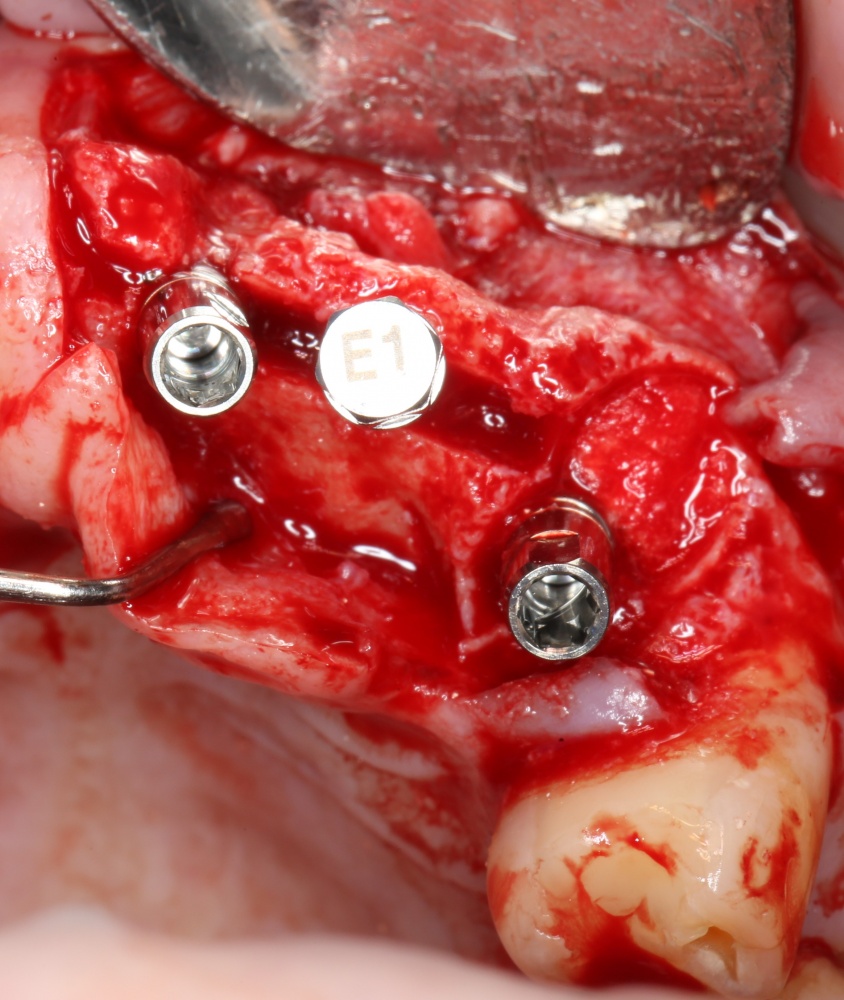

При горизонтальной остеотомии, на мой взгляд, удобнее использовать минипластины. Как я уже отмечал выше, в практике мы используем X- и H-образные минипластины под винты размером 0.9х4мм. Количество металла в разных условиях может быть разным — всё зависит от того, на каком этапе достигается полная неподвижность перемещенного костного фрагмента.

В какой момент это делать? Наверное, если Вы используете графт в виде твердого блока, то, мне кажется. разумнее сначала уложить графт, затем проводить фиксацию перемещенного костного фрагмента винтами или минипластинами:

И наоборот, если вы применяете графт в виде гранул (типа, Bio-Oss L), то, для начала, нужно зафиксировать костный фрагмент, затем укладывать графт.